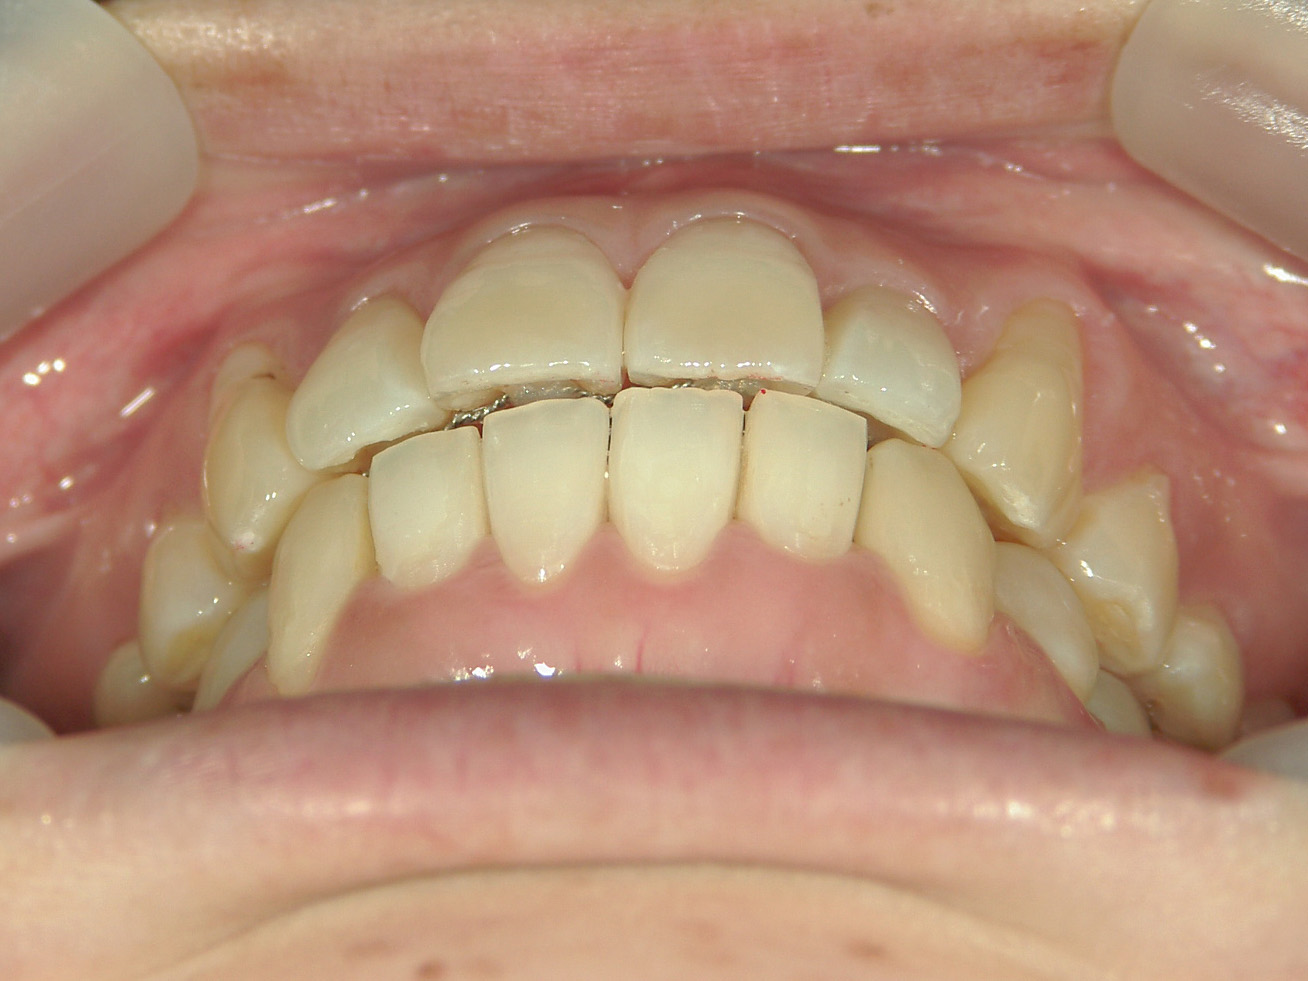

プチワイヤー矯正 症例(53)

主訴: 前歯の歯並びが気になる。

カテゴリー : ガタガタ(叢生)